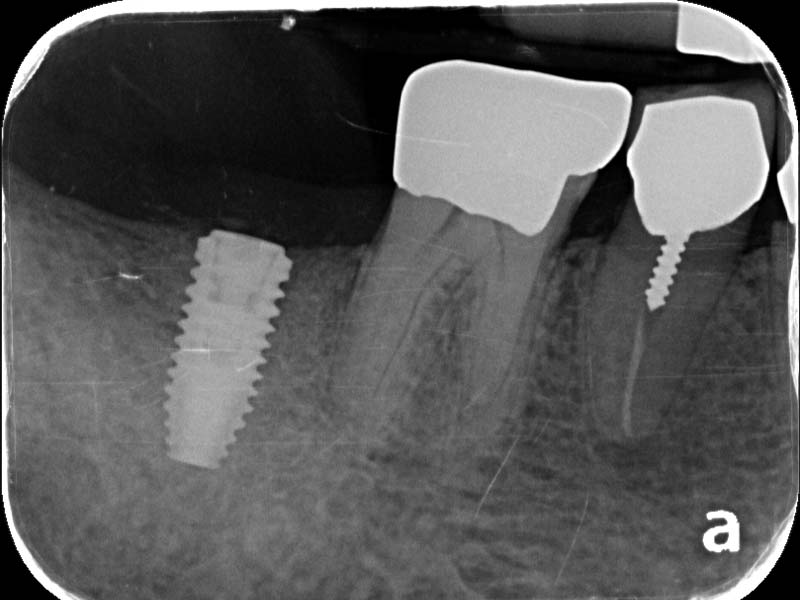

圖例為案例分享:

術前

植牙術後5.5個月